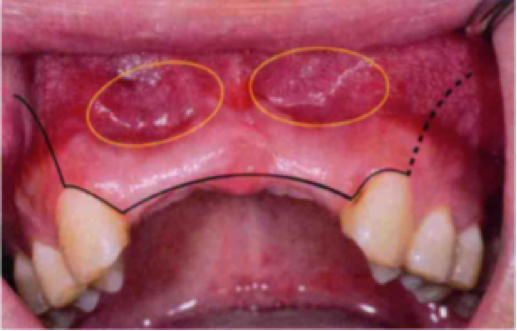

外置法植骨术(Onlay Bone Grafting)是指将块状骨嵌贴于受区骨面,增加牙槽嵴骨量的手术方法。 外置法植骨术是应用较多的骨增量手术,这种手术可有效地改善严重吸收牙槽突的高度和厚度,使原本不能种植或难以种植的患者拟种植区骨量达到满足牙种植的基本要求。

外置法植骨术(Onlay Bone Grafting)是指将块状骨嵌贴于受区骨面,增加牙槽嵴骨量的手术方法。外置法植骨术是应用较多的骨增量手术,这种手术可有效地改善严重吸收牙槽突的高度和厚度,使原本不能种植或难以种植的患者拟种植区骨量达到满足牙种植的基本要求。

高度应大于10mm,厚度应大于5mm,否则不适宜做种植,外置法植骨技术适用于牙槽嵴萎缩,残余骨量达不到以上要求的种植前治疗,不但适用于缺牙区宽度不足的唇颊侧植骨,也适用于垂直高度不足时的植骨。